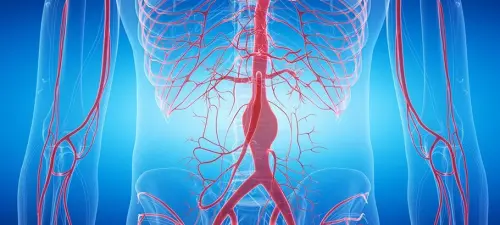

Аорта — найбільша артерія організму. Її черевний відділ починається нижче діафрагми і розділяється на рівні четвертого поперекового хребця на загальні клубові артерії. Саме тут найчастіше формуються аневризми: інфраренальний відділ — ділянка нижче ниркових артерій — уражається у 90% випадків.

Дуплексне сканування дає одночасно дві картини. B-режим показує стінку судини, наявність кальцинованих бляшок, пристінкового тромбу або розшарування. Доплер вимірює швидкість і характер потоку — дозволяє виявити стеноз гирл ниркових і клубових артерій, оцінити колатеральний кровотік. Саме тому метод є першою лінією діагностики як аневризматичної хвороби, так і облітеруючого атеросклерозу.